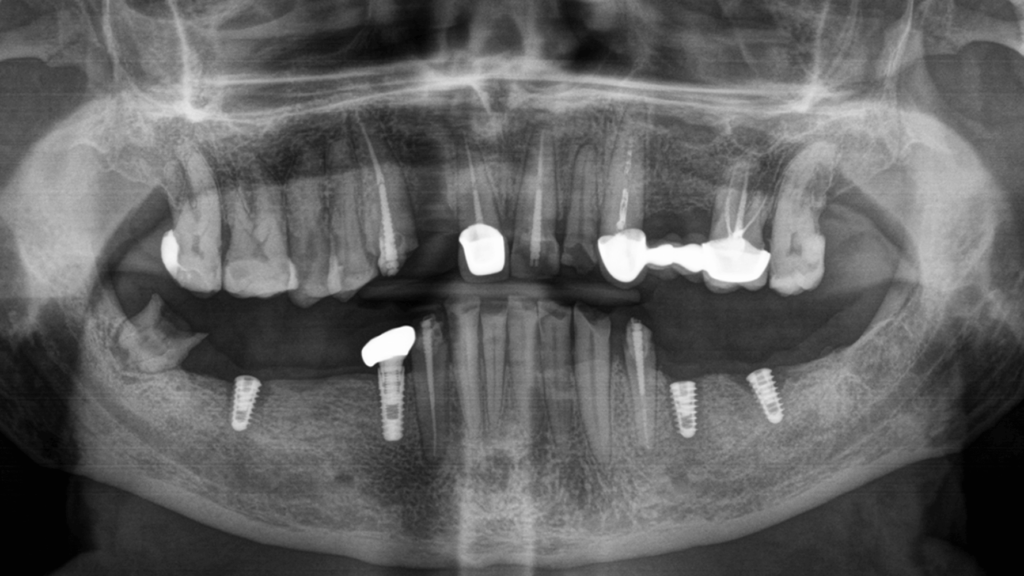

При осмотре пациента было обнаружено отсутствие восьми зубов: 5, 6, 7, 8 с правой и левой сторон на нижней челюсти. Нижние фронтальные зубы были поражены в результате патологического стирания вызванного массивной антагонистической конструкцией (металлокерамические коронки) на фронтальных зубах верхней челюсти. После 3D КТ-диагностики, осмотра и выслушав пожелания пациента, предложили следующий план лечения:

- Установка зубных имплантов в области зубов 5 и 7 нижней челюсти, по два имплантата с каждой стороны.

На первичной консультации врач провел осмотр полости рта, оценил КТ-снимки, составил план лечения и согласовал его с пациентом.